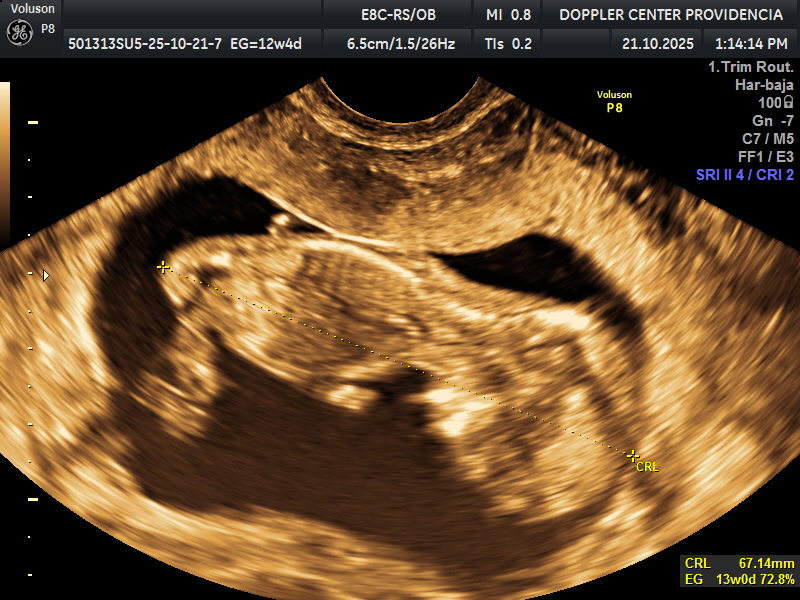

• Eco Doppler 11-14 semanas

Doppler Center